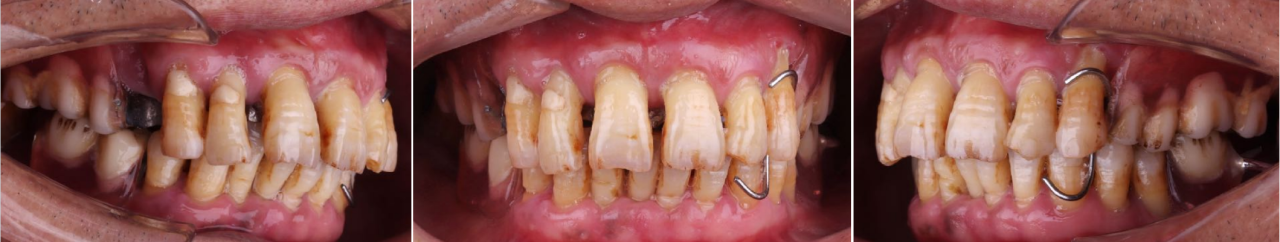

口外检查:面部对称无偏斜,面下1/3垂直高度正常,口角无偏斜,鼻唇沟加深,中线略偏右侧。低位笑线,前牙开唇露齿。开口度正常范围。

口内检查:13-23牙龈退缩,牙齿松动2-3度,14-17,24-27缺失,牙龈颜色质地正常。36,37,45,46,47缺失,下颌余留牙松动1-2度。